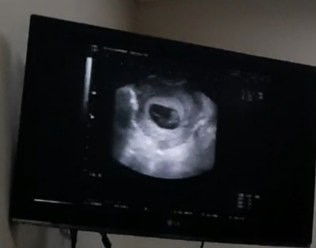

Bund, saya hamil 10 wk. Saat periksa ke dokter ternyata janin saya kecil sampai dikira masih 9 wk, saat dicek detaknya djj nya tidak ada. Ada yg punya pengalaman seperti saya? Jujur saya galau dan sedih, bingung baiknya gmn. Akhirnya janinnya memang meninggal, tp tidak dikuret. Saya biarkan luruh alami. #seriusnanya #firstmom #pleasehelp